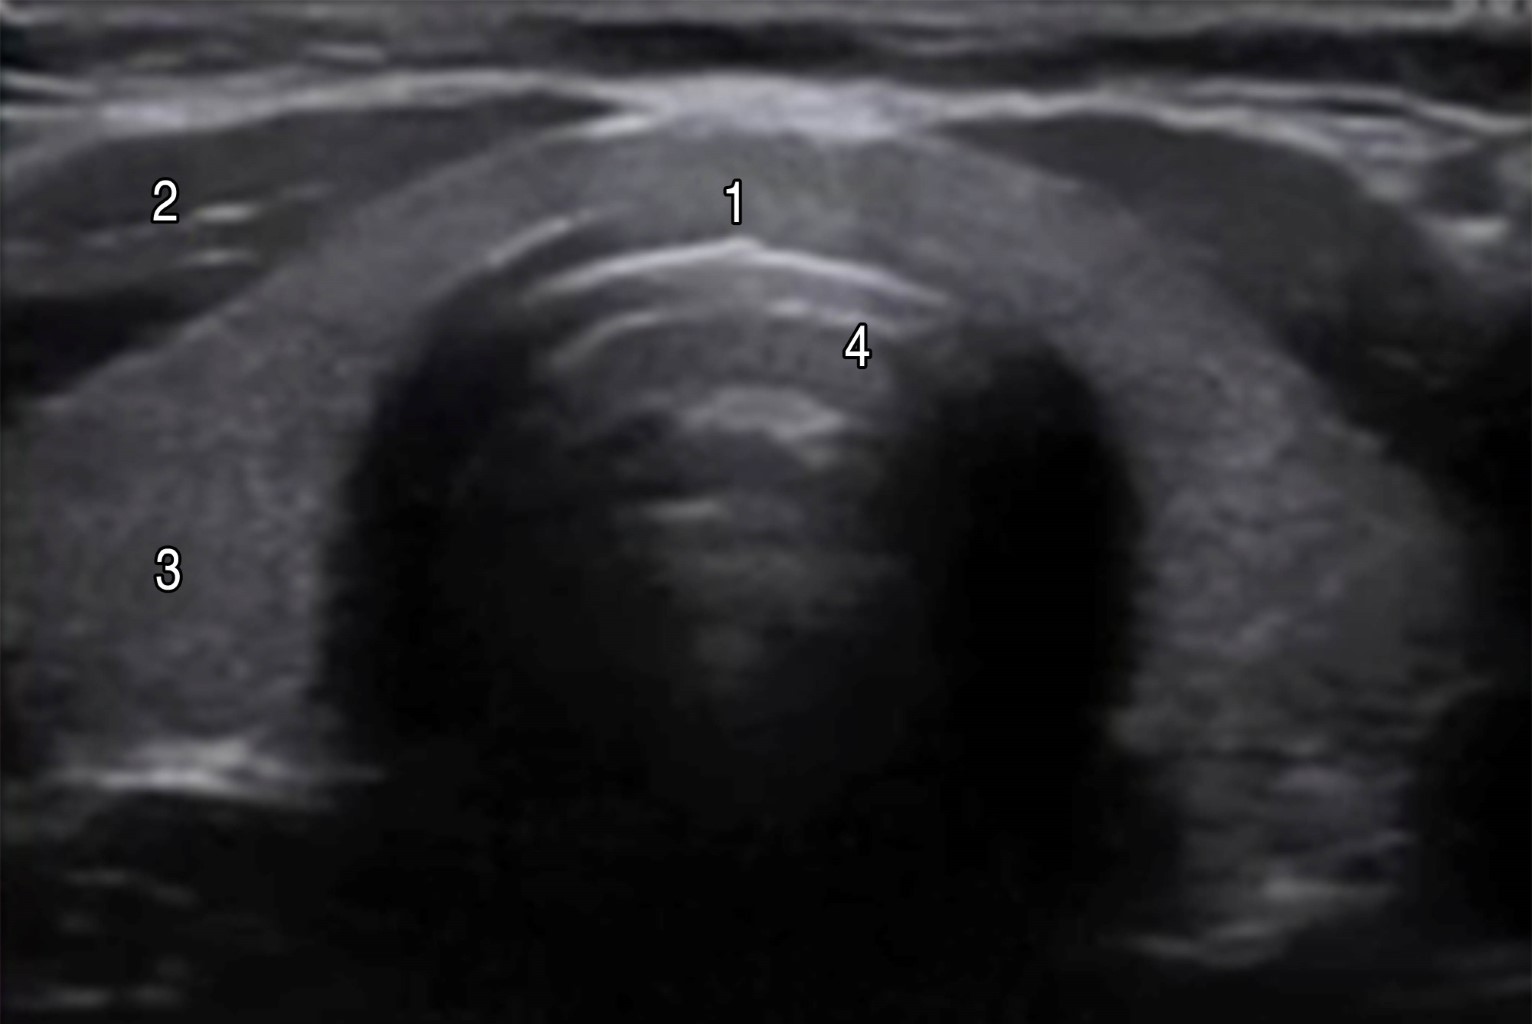

Ultrasonography is an active part of the clinical tools that we have in our arsenal for the evaluation of patients, and in the management of the airway, it can allow us to locate and mark the cricothyroid membrane prior to the management of a patient with a possible Difficult Airway. In trained hands allows the anatomy to be identified so that a cricothyroidotomy can be performed quickly and accurately in just 24.3 seconds. In this article, we show a rapid and visual systematic ultrasound localization of the cricothyroid membrane with an estimated time less than one minute. A linear high-frequency probe (5-14 MHz) should be used for exploration, as it is probably the most suitable for evaluating surface structures (within 0-5 cm below the skin surface). The positioning of the operator and the ultrasound scanner will depend on the patient's position, so in seated patients the operator is placed behind him and the ultrasound scanner in front of both, and in patients in a supine position, the operator is placed at the bedside of the patient and the ultrasound at the level of the right elbow.

Figure 5

Figure 6